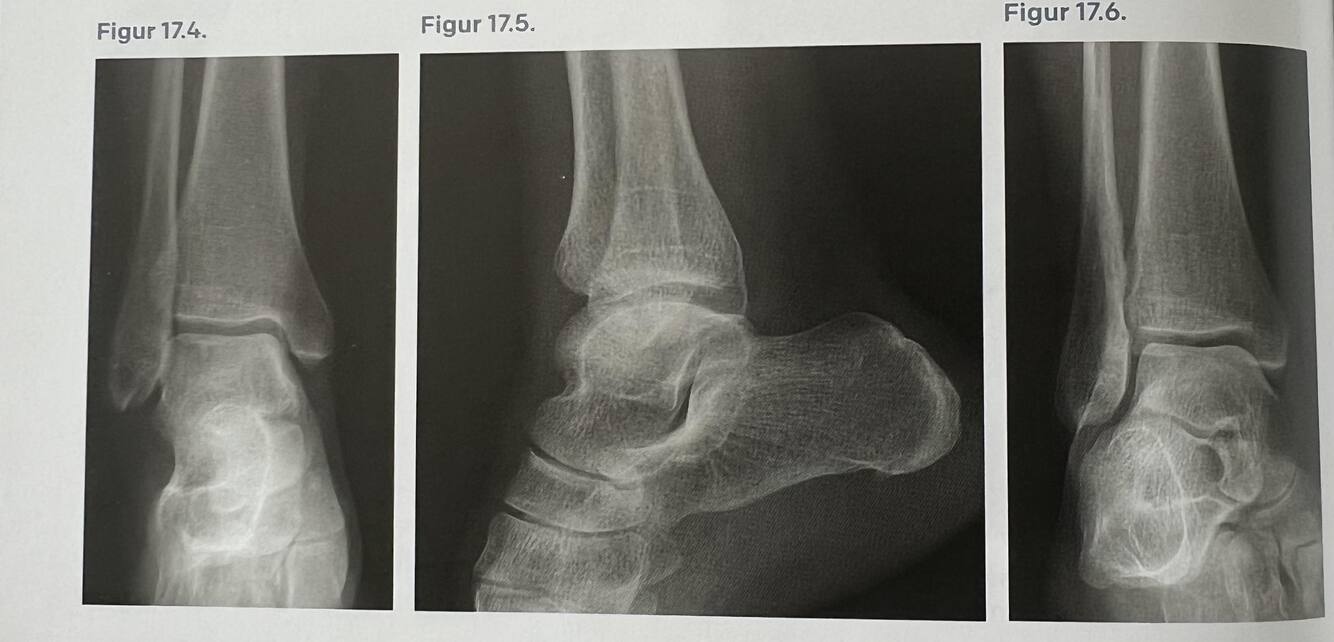

Du finder palpationsømhed sv.t. det anteriore talofibulare ligament. Behandlersygeplejersken har dog sendt patienten til røntgen og du får disse billeder.

Beskriv hvad du ser.

Der ses normal røntgenbillede uden fraktur, afrivninger, luksationer eller lignende.